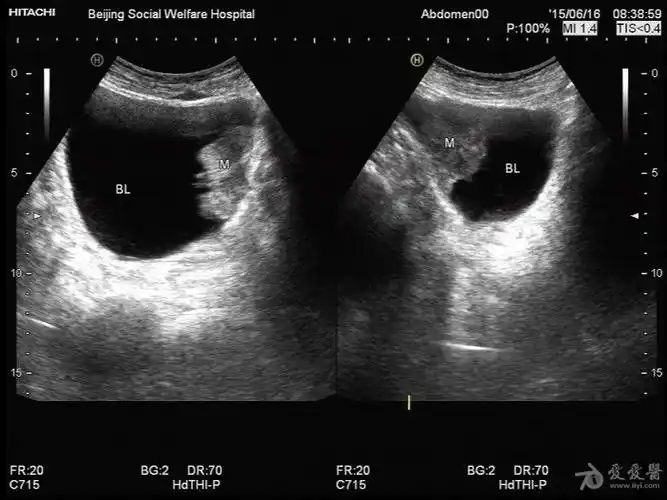

彩超提示膀胱内实质性占位病变,考虑膀胱肿瘤膀胱镜检示右侧壁菜花状

超声入门贴41-----膀胱癌

膀胱内实性占位考虑为膀胱癌

膀胱占位